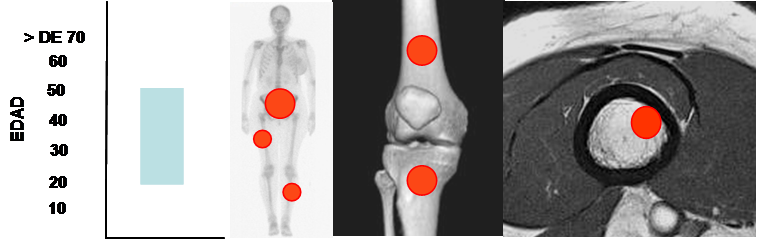

Se manifiesta entre la 3º y 6º década y tiene predominio en el fémur, la tibia y la pelvis. (Fig 107 A).

Fig 107 A. Fibrosarcoma.

Mayor frecuencia entre la 3º y 6º década. Predominio en huesos largos y la pelvis.

Lesión metafisodiafisiaria, de ubicación excéntrica.